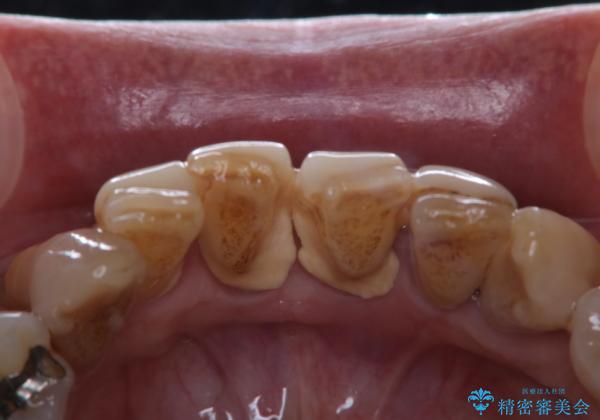

- 忙しくて、しばらくクリーニングをしていないため、全体的にしっかりとクリーニングしてほしいとのことでした。PMTC60分コースを行いました。

プラークが放置されると、そこで病原菌が繁殖し始めます。そうなるとバイオフィルム(歯面に強固に付着したばい菌の膜)になり、歯肉に炎症が生じ歯周病の引き金となります。

プラークやバイオフィルムといった細菌などを放置すると歯石となります。歯石になってしまうと歯磨きでは取り除くことができないため、歯科医院にて専門的な機械や材料を使用してクリーニングを受ける必要があります。